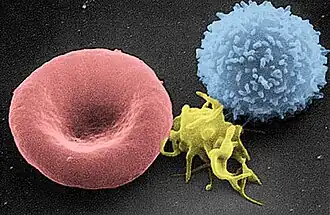

- A landmark study unveils a medical technique that renders T-cells resistant to HIV.[25][26]